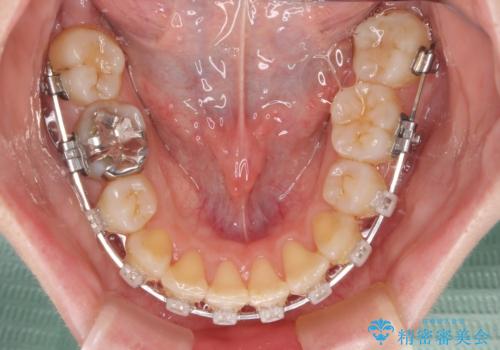

また、上顎臼歯は虫歯により抜歯されてから放置されている状態でした。

舌のトレーニングをしっかりと行っていただきながらワイヤー装置により矯正治療を行い、途中でインプラントを埋入し、矯正治療後に補綴治療を行うこととしました。